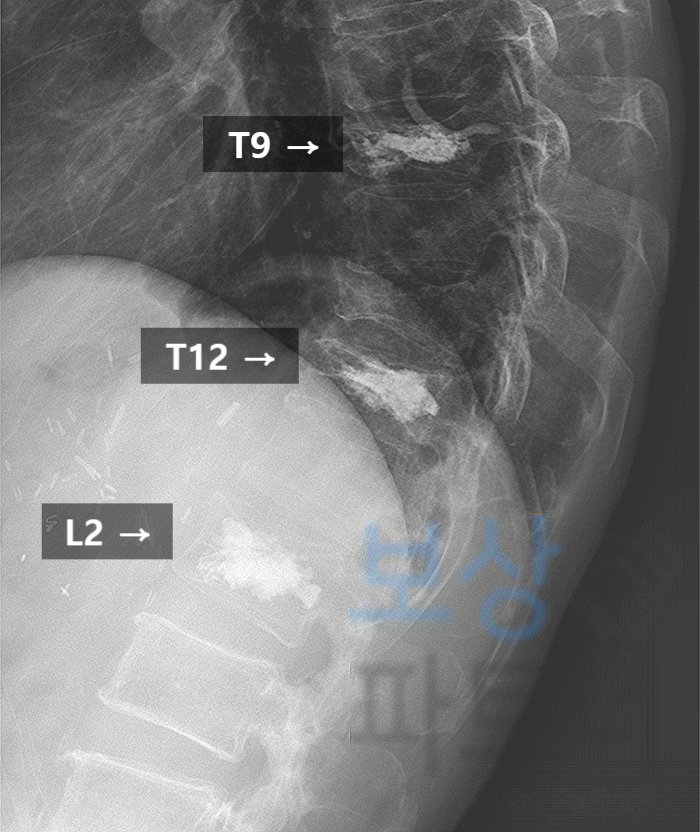

외상성 압박골절 흉추 9번, 12번, 요추 2번

[S22060, S22070, S32030]

이 사고로 고객께서는 3개의 척추체가 상당히 내려앉았습니다. 골밀도 검사 결과 심한 골다공증 상태이셔서 척추성형술(골시멘트술) 시행하기로 결정하셨습니다. 위 엑스레이 사진에 흰색으로 보이는 부분이 골시멘트 주입한 부위입니다. 다행히 시술은 성공적이었는데요.

제9, 11, 12번 흉추 압박율 각 48%, 47%, 46%

제10흉추 - 제1요추간 후만각 43도 측정됨.

보험약관상 '척추에 심한 기형을 남긴 때'(50%)에 해당함. 그러나 보상 담당자는 이러한 서류를 인정하지 않고 골다공증을 이유로 지급액 삭감을 주장하였지만, 오랜 손해사정 노하우로 적절하게 대처할 수 있었습니다.